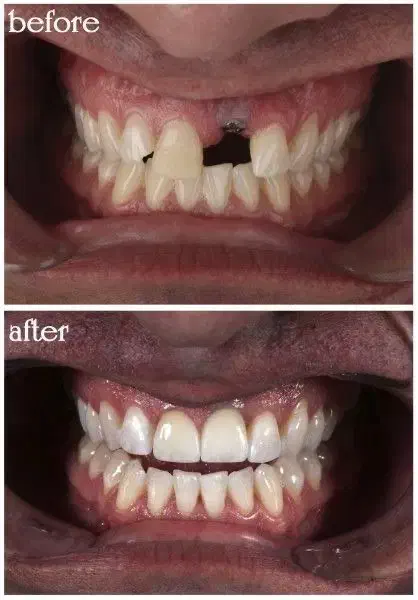

لبخند نو، قیمت استثنایی! دیگر نگران جای خالی دندانهایتان نباشید! جشنواره ویژه ایمپلنت در [گلفام] آغاز شد. ایمپلنتهای دندانی با کیفیت جهانی را با تخفیف بیسابقه و قیمتی باورنکردنی تجربه کنید. تخصص ما، لبخند زیبای شما. این فرصت محدود را از دست ندهید! همین حالا برای مشاوره رایگان تماس بگیرید. اقساط بلند مدت با ضمانت چک یا طلا + طرف قرارداد با تمامی بیمه ه**************] [فرهنگشهر بین کوچه ۲۷ و ۲۹ ]